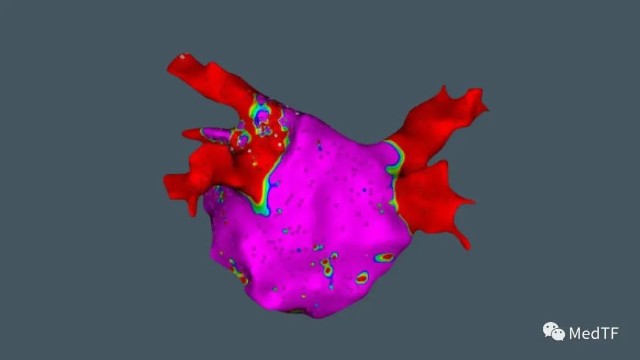

OCTARAY磁电双定位八分支星型标测导管是全球房颤治疗领域的颠覆性产品。OCTARAY用于房颤消融手术中关键的心脏建模环节,其八个分支上布满48个铂金电极,每一个电极都可以独立记录心肌的信息。以往心脏建模需要半小时,而这款产品短短10分钟就可以完成心脏上万个空间位置的录入,大幅缩短了房颤手术的时间。此外,导管的八个分支直径不到一毫米,且质地柔软,在心脏内操作时不损害心脏肌肉,保障手术安全。

OCTARAY优势

超高清晰度

以更高的精度和细节绘制地图,提高信号质量

更快速度

使用更多电极和独特的分支阵列,将映射时间缩短一半。

完美融合

与 CARTO 3完美融合,能够适用所有心房心室。同时与消融技术和超声技术完全集成。